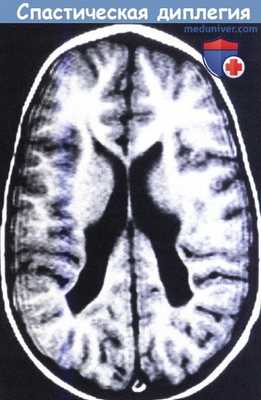

МРТ в Т2-режиме у ребенка со спастической диплегией. Задние рога боковых желудочков неравномерно расширены и вокруг них определяется утрата белого вещества.

Данный снимок характеризует позднюю стадию перивентрикулярной лейкомаляции и отмечается преимущественно у недоношенных детей.